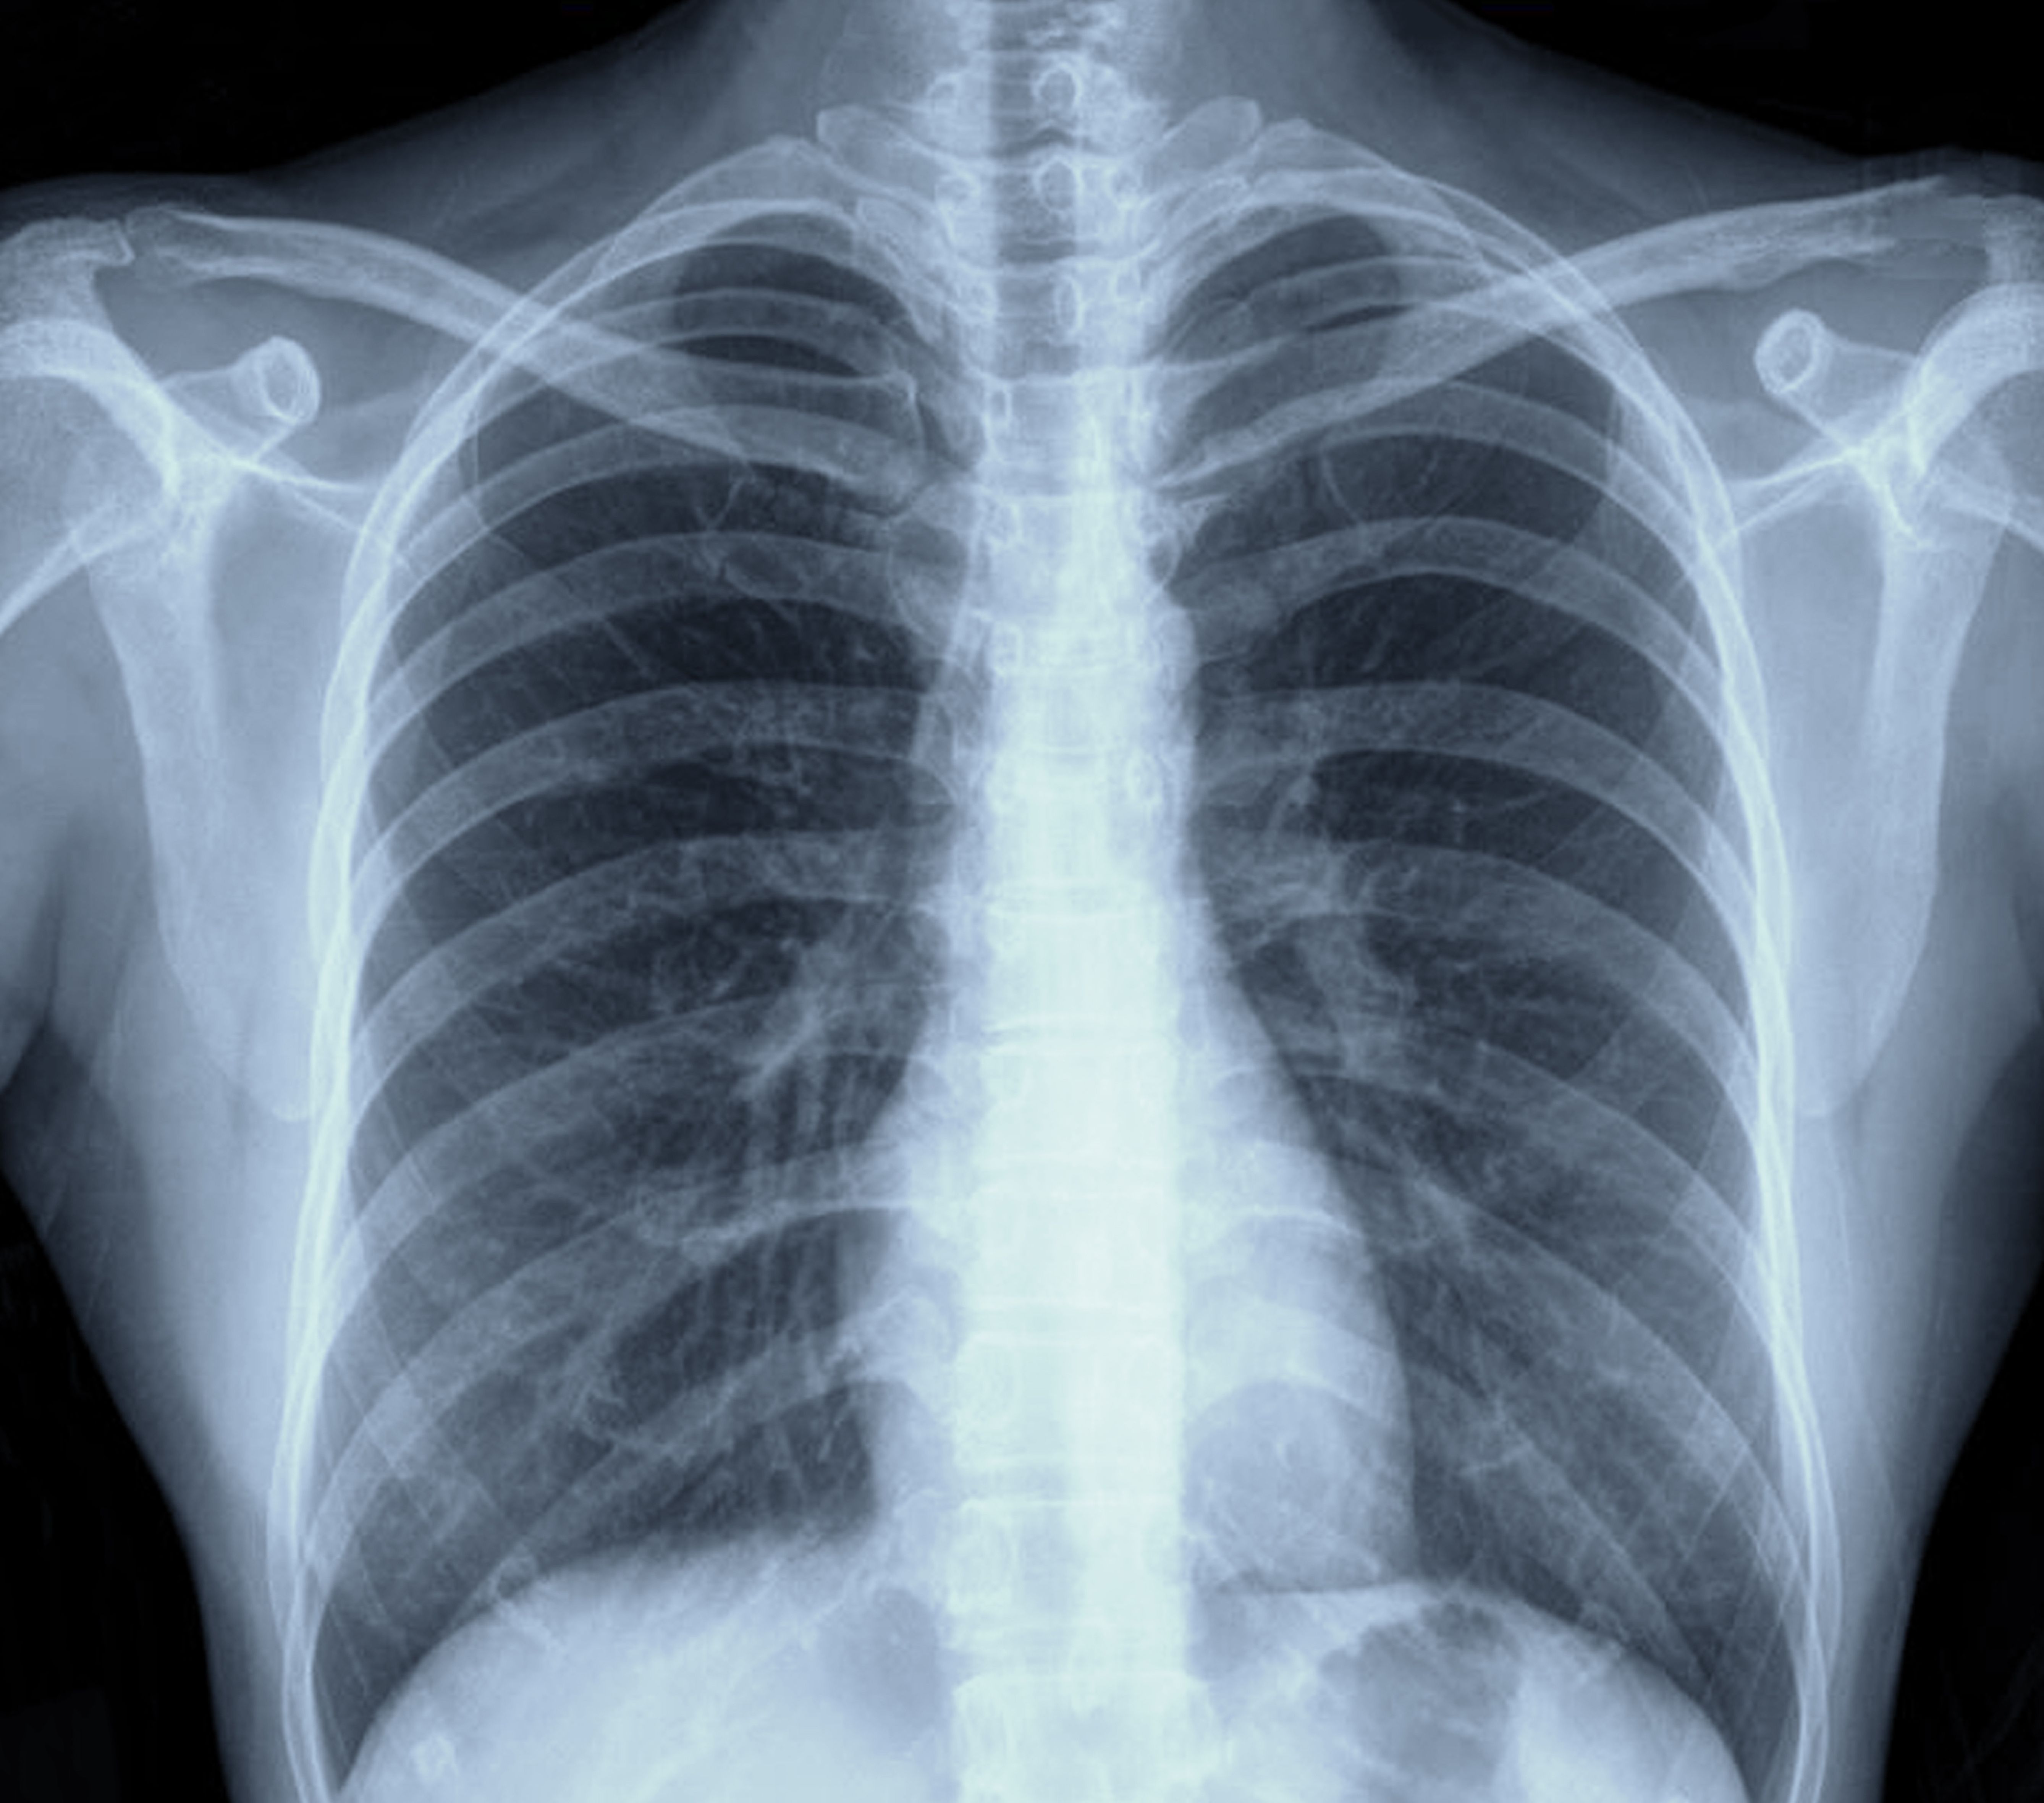

Panelists discuss how, at their practices, histology, staging and ECOG performance status guide treatment decisions for advanced non-small cell lung cancer (NSCLC). Compared with EMPOWER-Lung 1, these factors remain crucial. Key biomarkers, such as PD-L1 expression, influence PD-1 inhibitor efficacy. In 2025, treatment options are more personalized with emerging therapies.